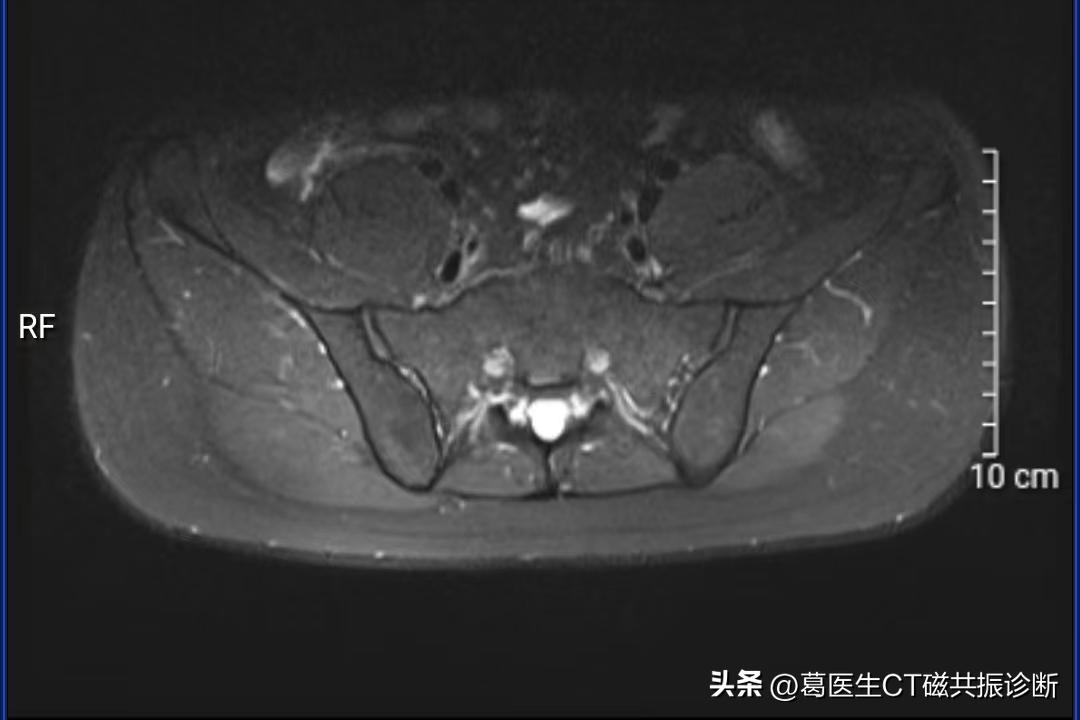

压脂序列,高信号消失(脂肪成分的特点)